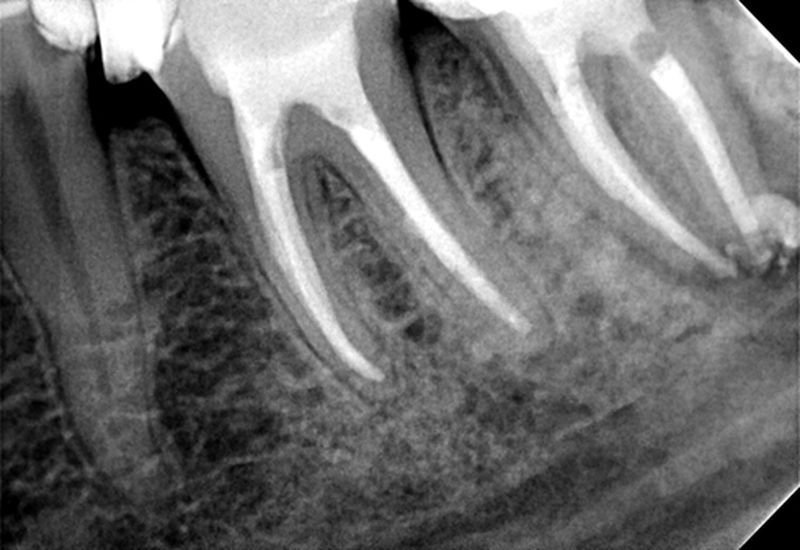

Stan po wypełnieniu ostatecznym kanałów korzeniowych poszczególnych zębów.